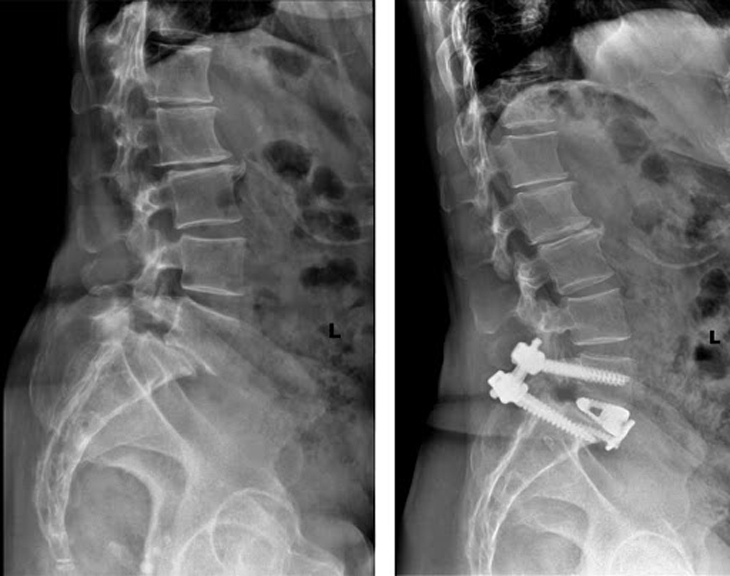

Trượt đốt sống Hình ảnh chụp X-quang trượt đốt sống

Theo dõi và điều trị sau mổ: sau mổ, bệnh nhân cần được bất động tại giường từ 5-7 ngày. Nếu bệnh nhân hết đau có thể cho ngồi dậy sớm hơn. Chú ý phát hiện biến chứng sớm: nhiễm khuẩn, tổn thương rễ... Cần chụp Xquang trước khi bệnh nhân ra viện để đánh giá vị trí của vít; đánh giá di lệch trượt sau mổ...